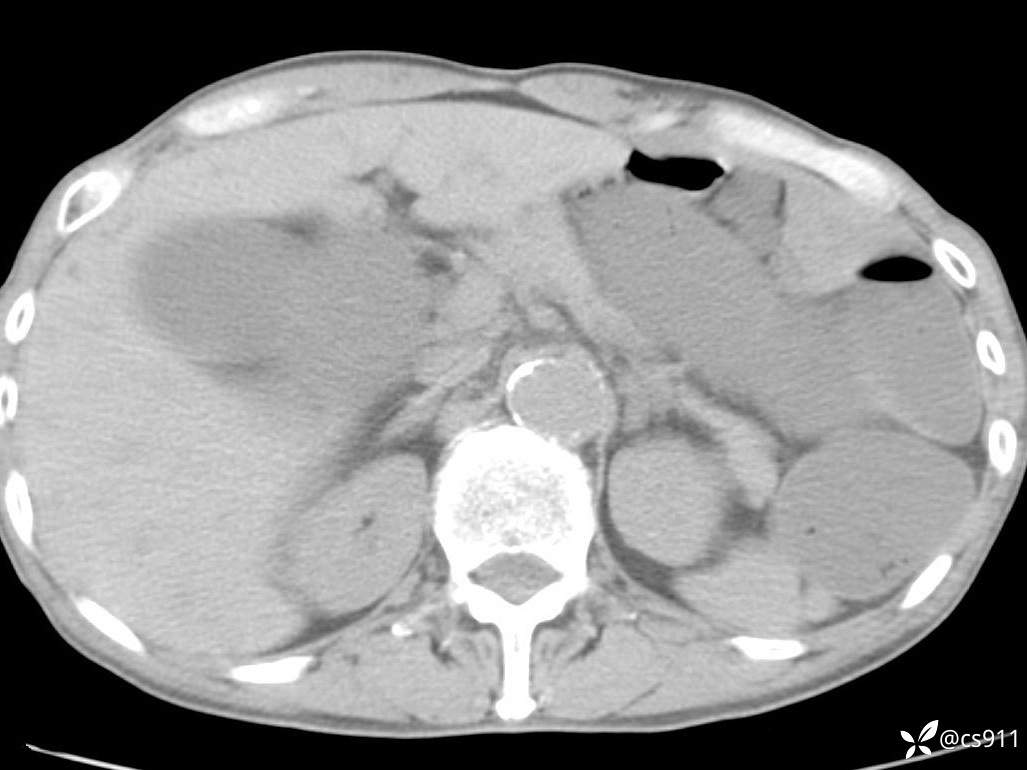

急腹症之急诊CT,原因?答案公布

男,77岁,腹痛、腹胀伴恶心呕吐1天。呕吐胃内容物,非喷射性呕吐,有咖啡色样胃内容物,诉有胃穿孔病史。查体:全腹平,下腹部压痛,全腹无反跳痛,叩诊呈浊音,移动性浊音阴性,肠鸣音减弱,1-2次/分。肛检:直肠未扪及明显肿物,可触及大量粪块。

T 36.6℃ P 80次/分 R 26次/分 BP 100/60mmHg

白细胞(WBC) H 14.55 10e9/L 4-10

中性粒细胞百分率(NEUT%) H 85.7 % 40-75

血淀粉酶(AMY) HH 1859 U/L 35-135

癌胚抗原(CEA) H 27.44 ng/ml 0-5

呕吐物 潜血试验 * 阳性 阴性

患者轮椅入室检查神志清楚, 能配合摆位和呼吸